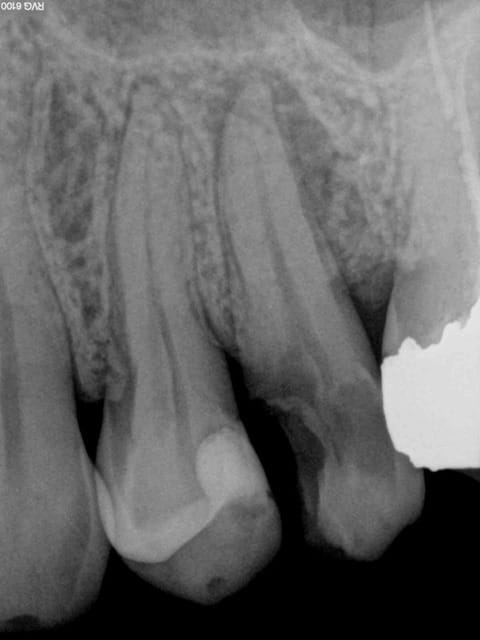

Et je termine la semaine avec un no post no crown; Le récipoc m'a un peu démangé je dois dire, mais ca n'est peut être que partie remise.-)))

Chicot29 : Par contre fêlure sur la 25 ? Ou tu viens de la coiffer ?

Pas fêlée, simplement le résultat d'une prévention gratuite et de soins gratuits.-)))

1 hkjoyv - Eugenol

Ben justement j'ai refait le composite parce qu'il y avait un problème de point de contact avec la couronne. Sur ce genre de cas le patient ne se plaignant pas j'ai tendance à fidéliser. Mais c'est sur il vaut mieux ne pas prendre de radios après les composites des fois on est décu, mais c'est trop tard.-))))